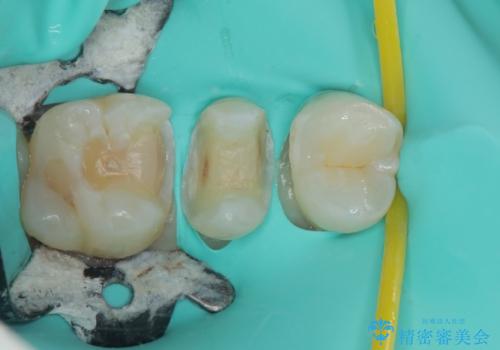

右下の6番目の歯は初診時から詰め物が大きかったため、被せものでの治療を提案していましたが、患者様の強いご希望でセラミックの詰め物(セラミックインレー)での治療をされていました。今回メインテナンス時に来院されたときに被せもの(オールセラミッククラウン)での治療を再度提案させていただき、患者様にも納得をしていただいたうえで、オールセラミッククラウンによる治療を行いました。

拡大鏡視野下で、セラミックの詰め物(セラミックインレー)、虫歯の除去を行い、オールセラミッククラウンに適した形に整えました。

歯と歯茎の間に圧排糸と言われる糸を入れてシリコーン印象材にて型どりをしました。